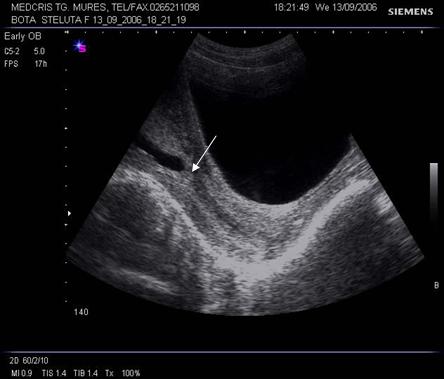

Fig. Nr.7. Sac gestational intrauterin ( cu sageata ) la ecografia transvaginala, coroana trofoblastica